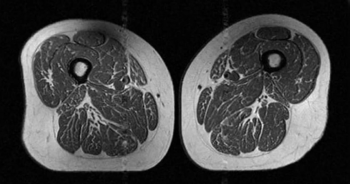

醫起看/大腿肌肉變「A5和牛」!研究:小心吃太多超加工食品

,支撐力就會下降,導致肌力衰退、走路速度變慢,進而影響整體的活動能力,還可能引發發炎反應及功能性影響,進一步損害關節健康。另外,研究也發現,考量到反映內臟脂肪分布的中央型肥胖,腰圍與大腿肌肉脂肪的關聯性比看BMI更明顯。至於什麼是超加工食品「UPF」?蔡明劼解釋,超加工食品通常是經工業化生產方法製造,並加入大量香料、著色劑、乳化劑等化學添加物,以增強保存期限與口感吸引力的食品。例如,碳酸飲料、包裝零食、即食餐點等,這類食物多半高鹽、高糖、高脂肪,但卻缺乏纖維、蛋白質與微量元素等必要營養。蔡明劼提醒「即使你的......